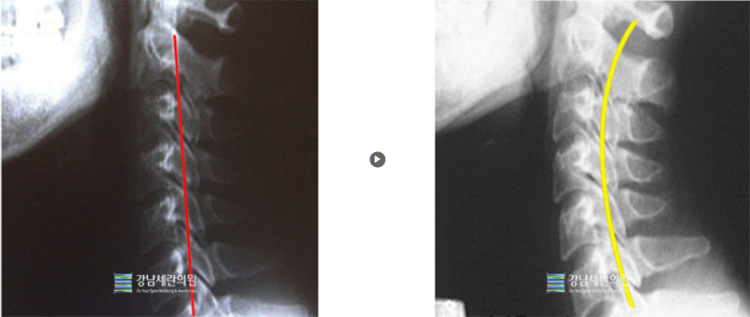

일자목 치료 전 ▶ 일자목 30회(3개월) 치료 후